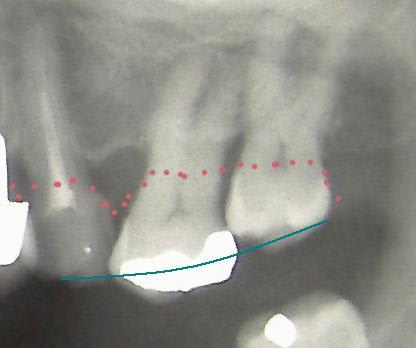

cf Radio: Patient de 60ans,la 26 a égressée++, et un pont est prévu au niveau de 35-36-37, mais il est évident que cette 26 gêne sa réalisation. Que faire ? la dévitaliser et la couronner? Son axe ainsi que le niveau osseux ne vont t-il pas poser un problème? (il n'y a aucun problème paro)

Hey j'ai justement le même cas que ci-dessus et l'égression est très importante, il était clair pour l'enseignant qu'il fallait extraire... Qu'en pensez-vous?

dans un cas comme , j'envoie maintenant systematiquement chez un confére qui a une kodak 9000D, histoire vraiment de savoir où en sont les furcations de la 16. Et j'ai souvent des grosses surprises que je ne voyais pas à la retro, mainetant même avec des debuts de frucations on peut quand même un onlay , mais le patient sera prévenu que sa dent va continuer a perdre de l'os, et la stratégie implantaire ne sera pas la même dans 10 ans